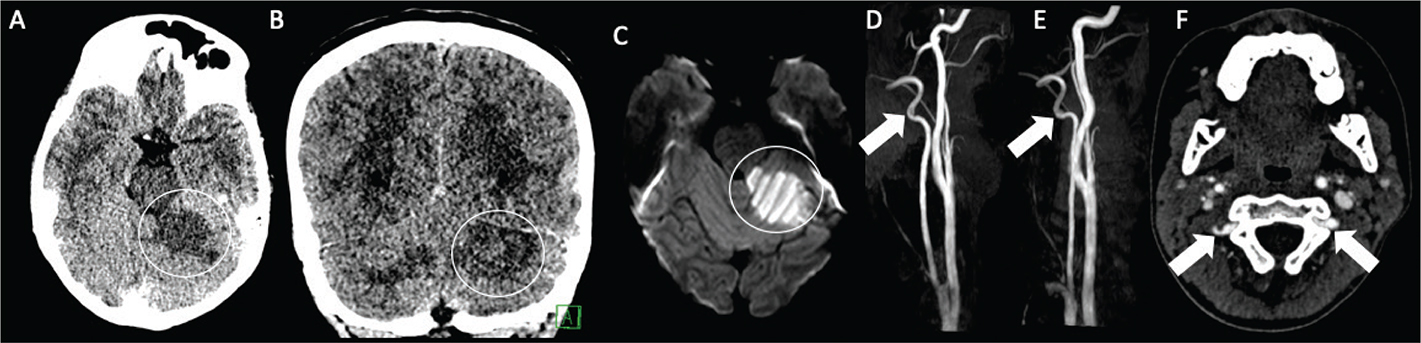

Fig 4

Figure 4. A 19-year-old female with a history of Down syndrome and repaired ASD and VSD. The patient presented with 2 days of aphasia, alerted mental status, and right upper quadrant field cut. Axial CT (A) demonstrates hypoattenuation with loss of gray-white differentiation in the left middle cerebral artery territory (black circle). DWI (B) and corresponding ADC (C) confirm acute left MCA territory infarct (white circle). MRA (D) demonstrates focal left MCA M2/M3 occlusion (arrow). She was found to be positive for Lupus anticoagulant.